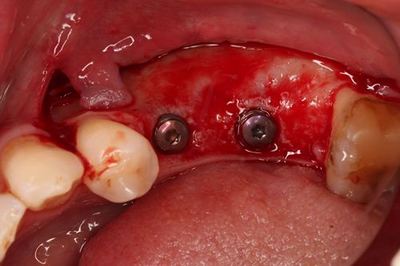

封鎖スクリューを締結し、インプラントフィクスチャーを保護します。

頬側部分の骨の陥凹部分に

ドリリング時の骨切削片とハイドロキシアパタイトを混和して填入します。

皮質骨にデコルチケーションした後に移植材を填入し馴染ませます。

粘膜弁の骨膜減張切開も行います。